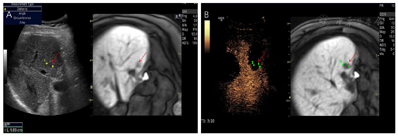

肝脏超声造影与增强MRI检查:S5、S8肿瘤呈"快进快退"表现,提示肿瘤复发。

根据患者的实际情况,MDT讨论一致同意行超声引导下微波消融治疗。超声-MR融合成像提示共4个病灶复发。S8有2个邻近膈面病灶,为保护膈肌及保证视野清晰,行人工胸水、人工腹水辅助,因腹腔粘连较严重,膈下腹水操作失败,仅行人工胸水减少肺气对视野的影响,从而进行超声引导下消融、超声造影-MR融合成像评估效果(图1);S5小病灶邻近门脉且灰阶超声显示不清,应用超声-MR融合成像定位引导消融,并使用超声造影复查效果(图2);S5大病灶邻近胃肠道,因腹腔粘连行人工腹水操作较困难,改为使用球囊隔离技术将肝肿瘤与肠道分离,在保证肠道安全的情况下行超声引导下消融,并行超声造影-MR融合成像评估效果(图3)。